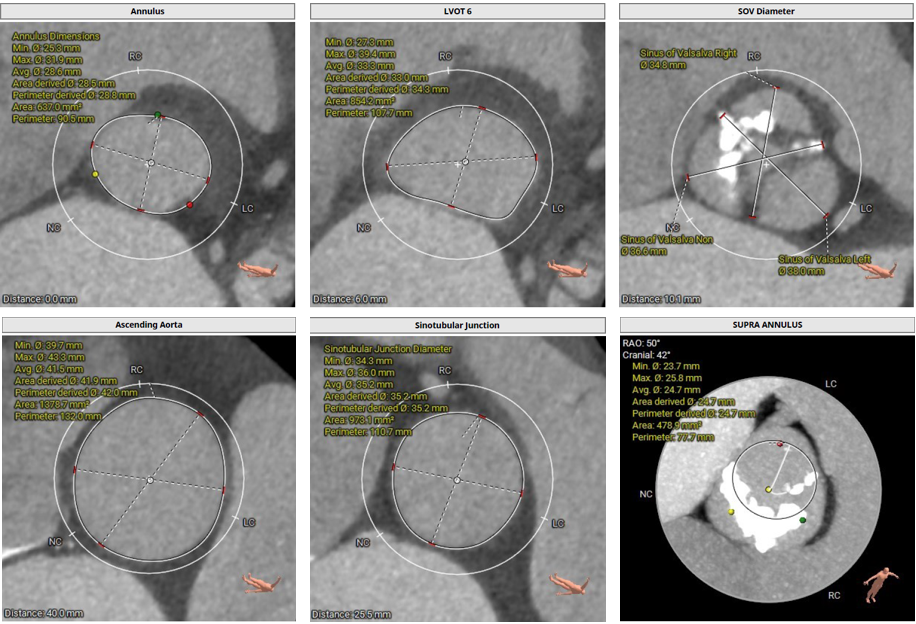

术前CT评估:

• Type1型二叶式主动脉瓣,R-N窦钙化融合嵴,瓣叶重度钙化伴增厚,L-N窦局部粘连。

• 冠脉开口高度可,左冠瓣叶稍冗长,左冠切线位瓣叶长度>冠脉开口到瓣叶附着缘距离,右冠切线位瓣叶长度<冠脉开口到瓣叶附着缘距离。

• 瓦氏窦、窦管交界内径可,升主动脉扩张,左室腔内径增大。

• 瓣环水平夹角46° ,主动脉弓宽度、角度尚可。

主动脉根部测量

冠脉阻挡风险评估